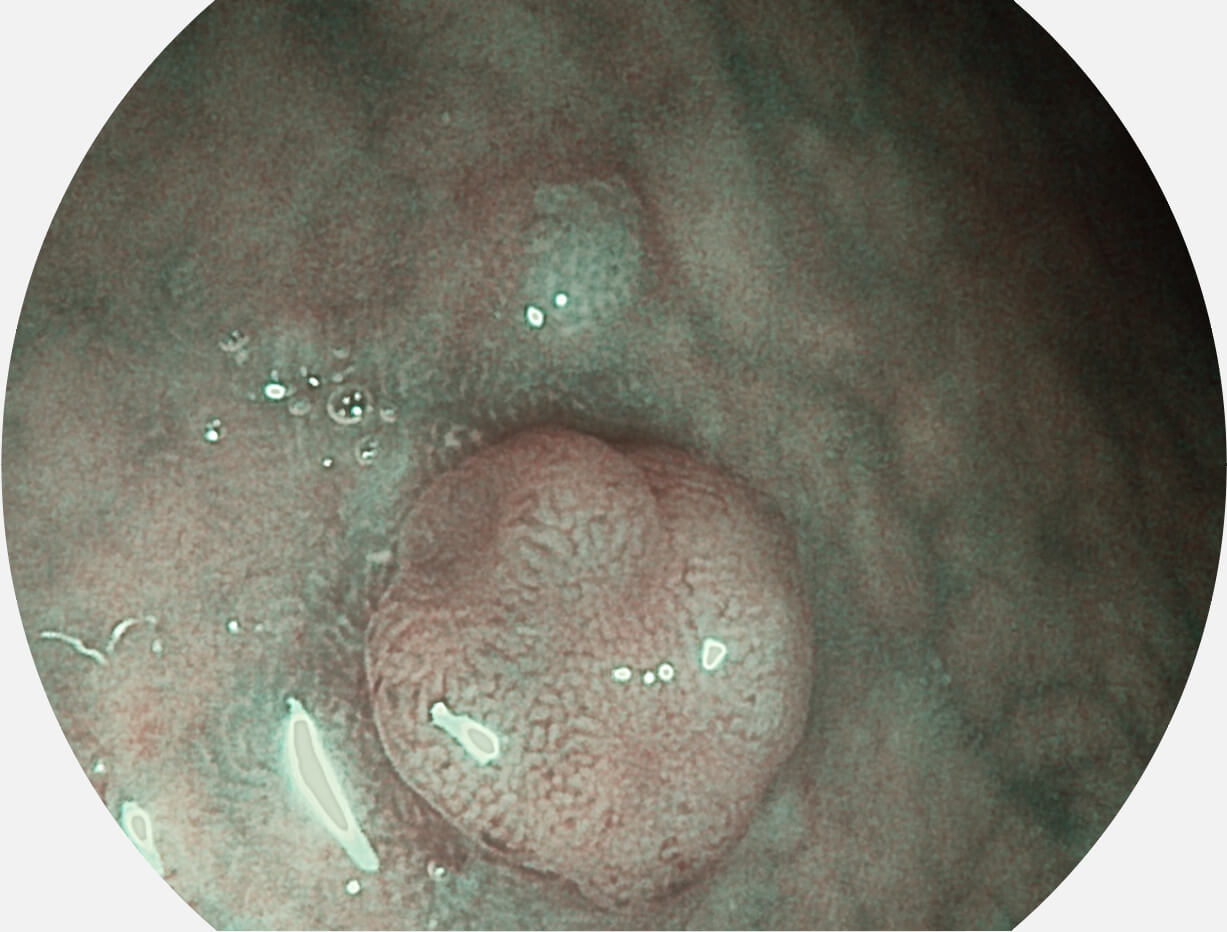

Spectral Focused lmaging, SFI

图像具有高亮度、高黏膜血管颜色对比度的特点,且不改变粘液、食物残渣、粪便的基本颜色,可在中远景下进行观察,助力消化道早期疾病的诊断。

SFI图像